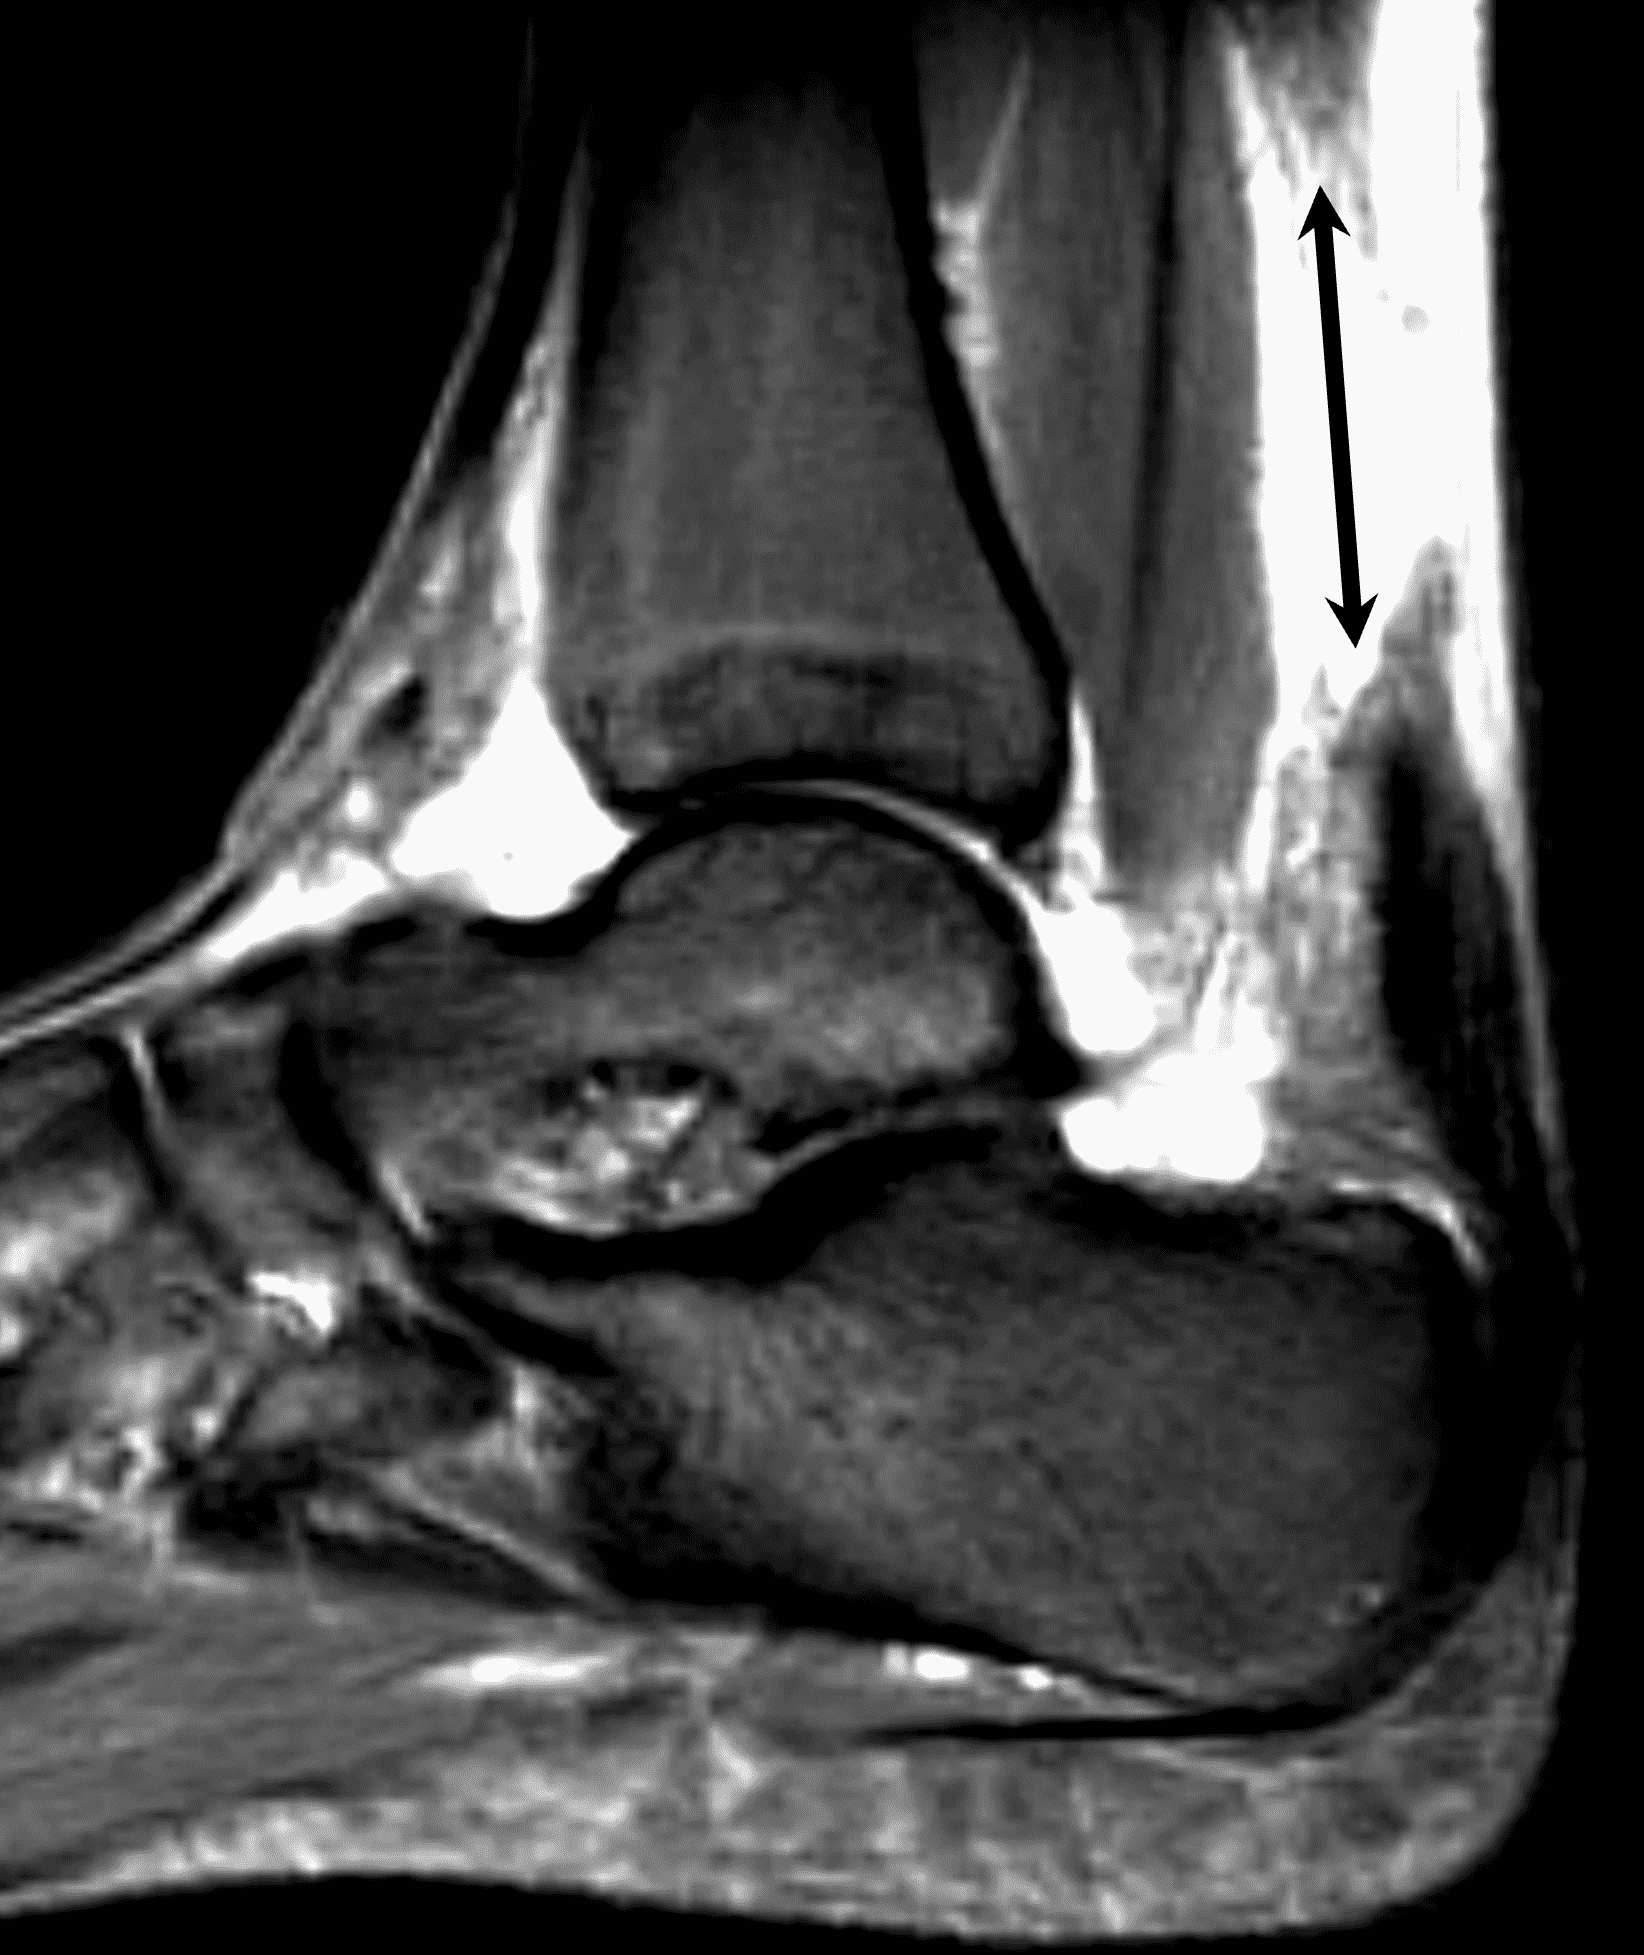

Figure 2: Complete Achilles tendon rupture. (2A) The lateral radiograph shows a thick and indistinct proximal Achilles tendon contour (arrows). (2B) A fat-suppressed T2-weighted image shows complete rupture of the tendon with a fluid-filled gap (yellow arrow) measuring 1.5 cm in length, located 10 cm cranial to the tendon insertion (blue arrow) and just distal to the edematous myotendinous junction (red arrow). The tear is superimposed on diffuse tendinosis. (2C) A sagittal T1-weighted image confirms the diffuse tendinosis. Fluid extends anteriorly into Kager’s fat pad (arrow) suggesting disruption of the anterior paratenon. (2D) A transverse fat-suppressed T2-weighted image through the proximal tendon shows no intact fibers (arrow), confirming the full-thickness rupture.

Acute, complete Achilles tendon rupture just distal to the myotendinous junction, superimposed on diffuse tendinosis.